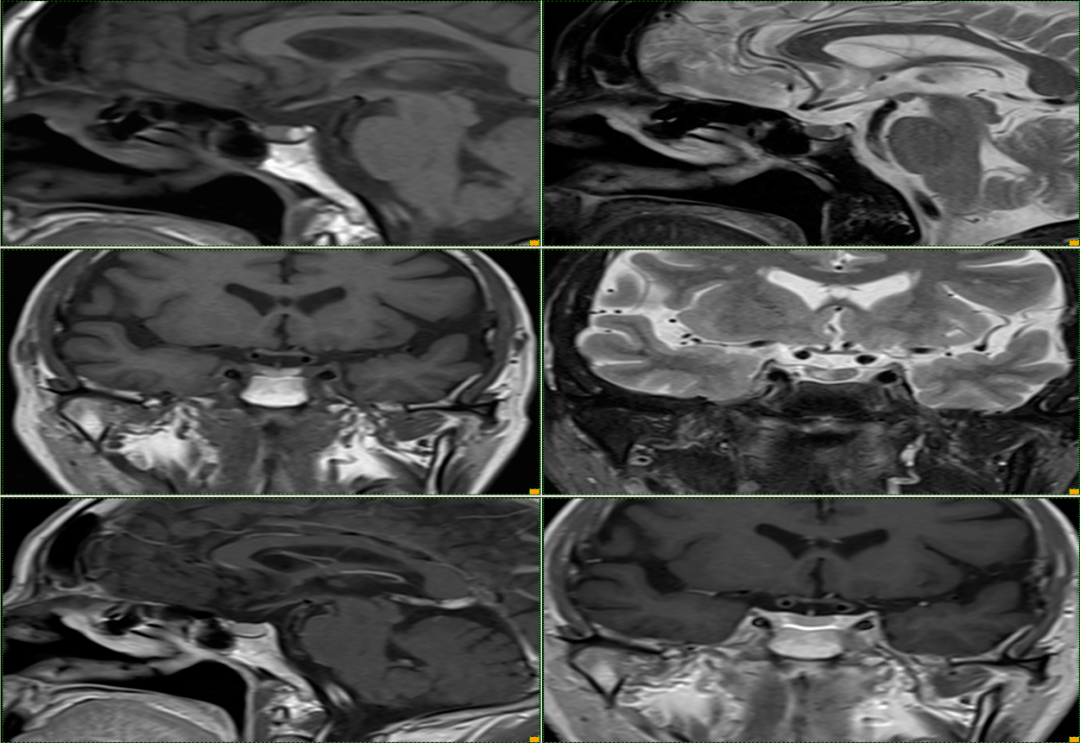

t1wi 高信号的神经垂体前方case 5:m/52y矢状位 t2wi 示:高信号囊肿和

c)显示垂体间质部(箭头)附近t2高信号和t1低信号的无增强的囊肿(箭头)